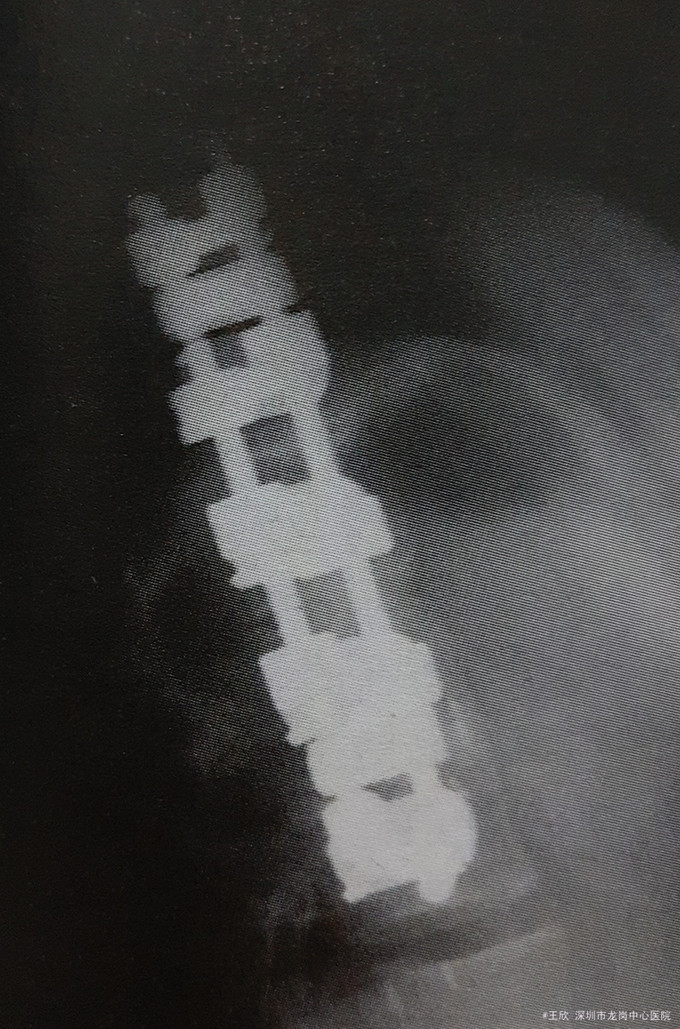

女孩,16岁,脊柱侧凸融合术后,腰背部疼痛进行性加重1年。患者因青少年特发性脊柱侧弯行融合术后1年左右到脊柱外科就诊。13岁时第一次出现背部疼痛和脊柱侧畸形,T11〜L3左侧成角36°,Riser征Ⅲ度。1年后,侧发展为45°,行前路T10〜L3椎间盘切除,自体肋骨椎体间融合,前路T11〜L3Kaneda器械内固定术。术后患者症状缓解明显。不过,近8个月以来,患者逐渐出现背部疼痛并进行性加重,伴活动后背部肌肉痉挛。患者否认近期外伤史、神经症状和大小便异常,无发热、寒战和体重改变。

体格检查 一般状况:神志清楚,査体合作,独立行走;四肢:毛细血管充盈良好,无杵状指、发绀和水肿;肌肉骨骼:椎旁肌无明显触痛,无明显肌肉痉挛和萎缩,四肢肌力5级并左右对称,针刺觉和轻触觉正常,深肌腱反射2+、左右对称,双侧直腿抬高试验阴性,踝阵挛阴性;皮肤:背部正中术后瘢痕,愈合良好。 实验室检查:胸腰段X线检査如图

诊断:腰椎假关节形成 治疗:X线检查示局部骨形成不完全,患者需要再次手术行“后路脊柱融合、器械内固定术。”